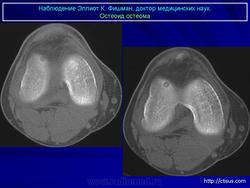

При рентгенологическом исследовании остеоид-остеома обнаруживается как субкортикально расположенный участок окостенения, окруженный ободком остеосклероза, ширина которого увеличивается по мере прогрессирования опухоли. При этом центральная часть опухоли становится менее заметно. Граница между центральной светлой зоной и склеротическим ободком, отчетливая в ранний период, со временем стирается вследствие того, что центральная зона опухоли подвергается оссификации и обызвествлению, которые распространяются центробежно. Рост кортикальных и субпериостальных остеоид-остеом сопровождается также реактивным склерозом- Имеются указания и на то, что если новообразование растет в костномозговом канале, то в соответствующей кости развивается остеопороз. Обычно опухоль легко вылущивается из окружающей кости и макроскопически представляет собой мелкозернистую, красновато-бурую костную ткань. Остеоидную остеому, как правило, удаляют хирургическим путем. Рецидив возможен, но практически не встречаются. Если он и происходит, то спустя 10 лет и позднее после удаления первичного узла опухоли.

Рентгенологическая картина. На обзорных рентгенограммах очаг поражения характеризуется утолщением и уплотнением кортикального слоя кости вокруг небольшого литического гнезда.